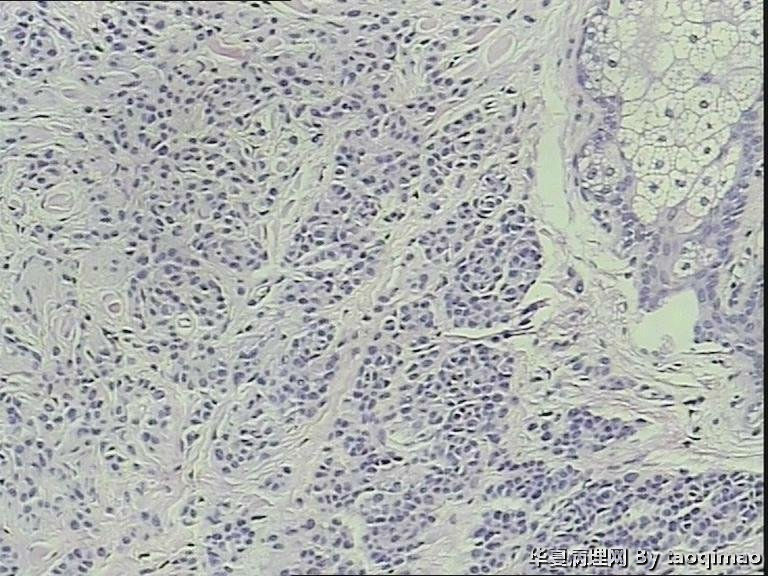

两例头皮肿物有差别么

• 两例头皮肿物有差别么图2

图2

第一:皮内痣 第二:皮内痣并表皮囊肿

都要考虑皮内痣。实在有差别就是第2例上有表皮囊肿,容易伴发。

皮内痣,第2例伴表皮囊肿,1处于退化期,倒是该学学

第二例合并的有个小的表皮样囊肿,或说粟丘疹。

灰白色,我想是由于有的皮内痣本身没有太多色素吧,不少皮内痣是皮色的。你的俩病例,片子里都没啥见到色素,应该可以解释了吧。

头皮皮内痣常呈皮赘样,质软有蒂,很多时候退化后呈正常肤色,切片中常有成熟的脂肪细胞,临床很容易误诊,诊断皮内痣应该没有问题的!

这个患者女,24岁,右颞部头皮肿物 24年,带皮的组织一块1.7x1x1,突出于皮肤表面,灰白色肿物,剖面实性灰白,请各位老师给帮忙诊断一下,这两个病例是同一个诊断么